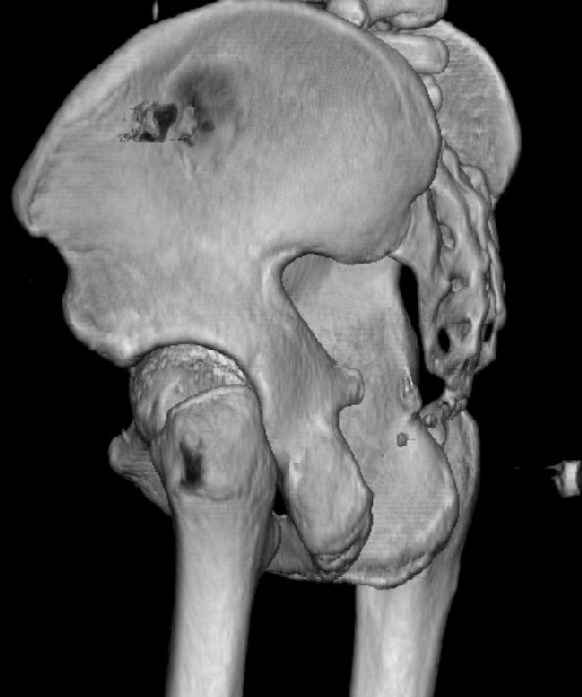

The last two images from the 3-D CT scan certainly makes the fracture look worse than the plan radiographs.

Might have to reconsider my suggestion to leave it alone at this stage.

The joint is non-concentric as the head appears to be either "following the caudal segment", or the dome component is displaced from the tethered head... or so it seems... and he's young... so, many fracture surgeons would recommend reduction and fixation.

So we must decide preoperatively which part is the displaced segment?

It's difficult to know from these few selected images which component of the injury (was before and now) should be deemed the "soon to be mobile"

segment. It's my best guess that it is the caudal portion and there exists a healing fracture line somewhere thru the posterior column...one image

suggests it. If true, its early healing/union should be disrupted, and the resultant fragment mobility then allows accurate reduction.

Such work is not always possible using a single exposure... it's not unreasonable to first access the healed zone and osteotomize it using one direct exposure, then turning the patient if necessary to use another opposite exposure to further mobilize the fracture, reduce, clamp, and fix it.